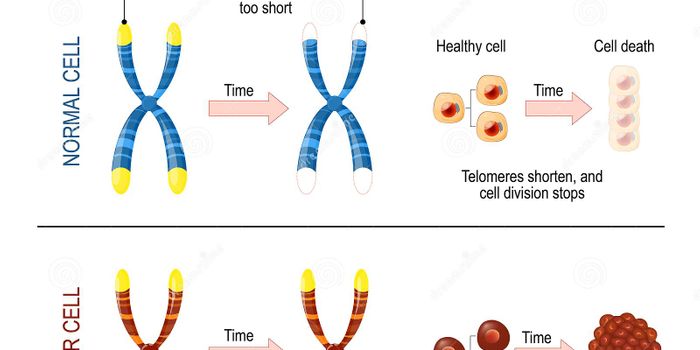

SEP 06, 2019Drug Discovery & DevelopmentIn the last 100 years, life expectancy in the US has risen from 55 years until 79 (Roser: 2019). And with the continuous ...

SEP 15, 2019ImmunologyNew research shows a transcriptase that helps time cell death varies in expression, and is unusually localized, in cance ...